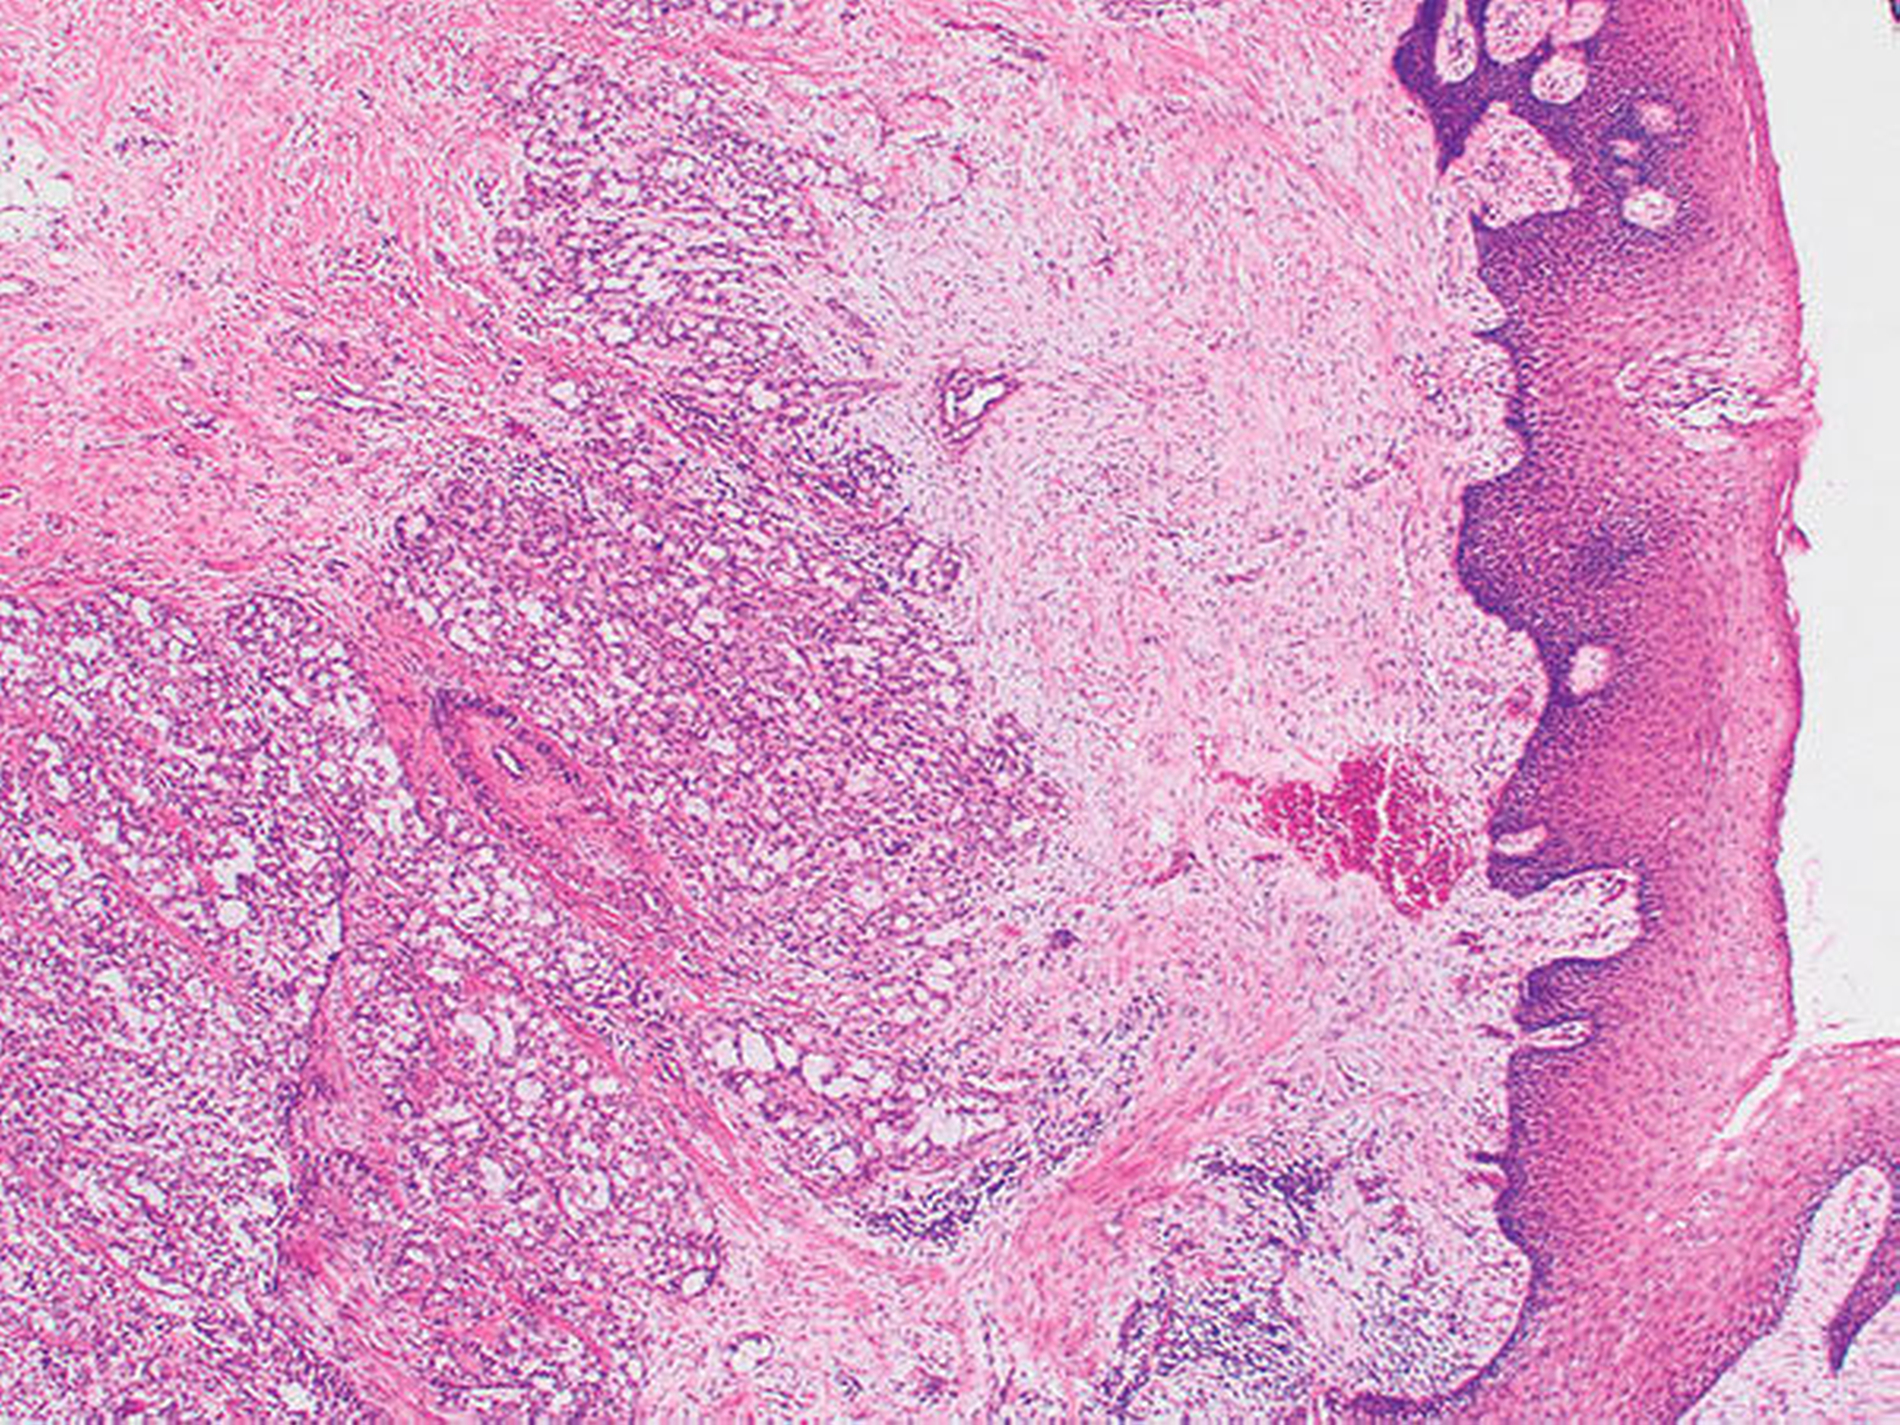

Die histopathologische Beurteilung des Resektionspräparats ergab einen 0,5 cm x 0,6 cm x 0,5 cm großen, ulzerierenden, läppchenartig aufgebauten Tumor mit soliden, mikrozystischen und tubulären Strukturen (Abbildung 3). Es zeigten sich weder Lymphgefäßeinbrüche noch eine Perineuralscheideninfiltration. Die Mindestabstände des in toto resezierten Tumors waren zur Tiefe (zum Knochen) unter 0,1 cm, nach lateral 0,3 cm und nach medial 0,7 cm, nach anterior sowie nach posterior mindestens 0,7 cm. In der ergänzenden Immunhistochemie zeigten Mammoglobin, CK7, GATA-3, GCDFP-15 und S-100 eine Co-Expression. In der Zusammenschau der Befunde wurde der Tumor nach aktueller TNM-Klassifikation von 2017 als pT1, pNX, L0, V0, Pn0, R0 (Mamma-analoges sekretorisches Karzinom) klassifiziert.